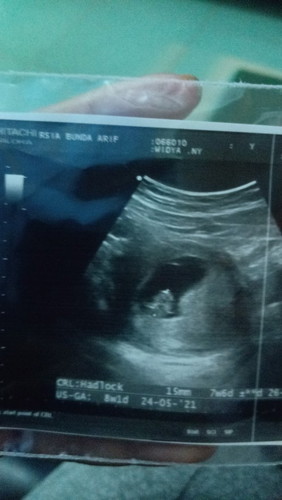

Saya baru banget tadi malem USG 8w alhamdulilah udah ada janin dah udah gerak-gerak gitu. Tapi tadi pas bangun tidur saya kan pake pantyliner eh taunya bercak darah coklat merah gelap agak banyak terus maaf pas pipis agak netes gitu warna merah gelap. Menurut bunda ini langsung ke dokter apa istirahat dulu beberapa hari kalau masih flek baru ke dokter ya Bun? Soalnya hamil aank pertama jadi takut😩#seriusnanya #bantusharing #firstbaby